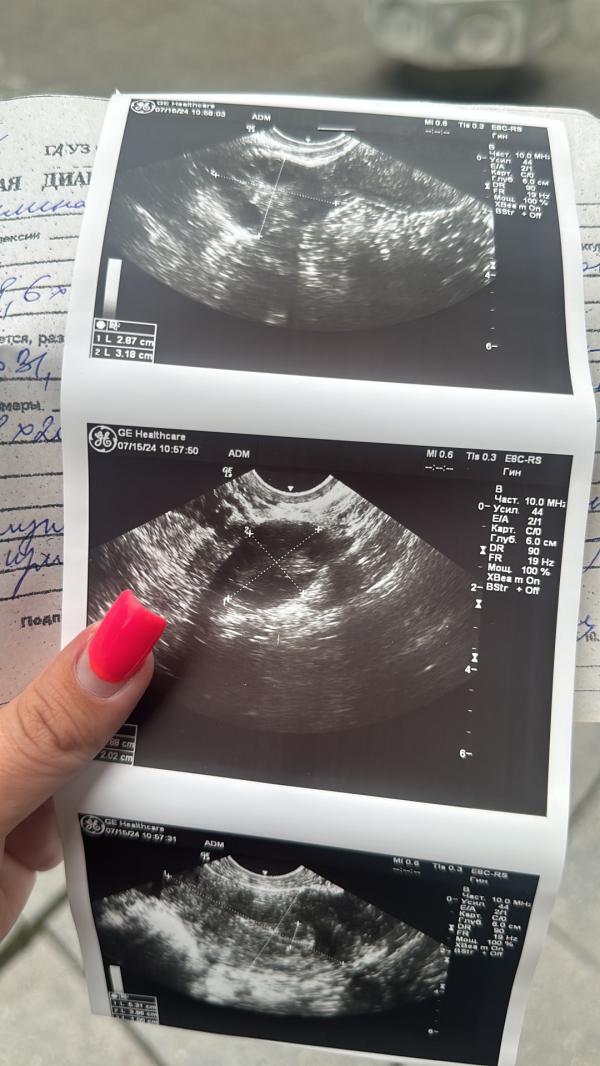

Срочно в больницу - что случилось, поеду в Гармонию узнавать?

Сказали срочно в больницу

Вам узист написал диагноз аденомиоз.

Лучше съездить в приёмный покой. Не ждите пятницу, не затягивайте

@aglaya.ivanovna, крч у меня опухоль в матке ?